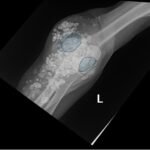

Calcinosis cutis is a condition in which calcium-phosphate salt deposits are formed in cutaneous and subcutaneous tissue. A subtype, metastatic calcinosis cutis, can occur in patients with disorders that cause hypercalcemia or hyperphosphatemia such as end stage renal disease. We present a case of a 67-year-old man with end-stage renal disease (ESRD) on dialysis who presented to the emergency department with a draining left elbow wound. On exam, he had irregular, firm nodules palpable in the subcutaneous tissue of both large and small joints. The presence of calcinosis cutis on imaging and lack of other findings suggesting infection led to outpatient wound care treatment. Recognizing the appearance of calcinosis cutis on imaging and conditions that present with calcinosis cutis is important for the emergency physician.